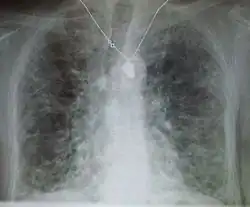

Plicní fibróza (doslova "zjizvení plic") je onemocnění dýchacích cest, v němž vznikají jizvy v plicní tkáni, což vede k vážným problémům s dýcháním. Vznik jizev a hromadění přebytečné vláknité pojivové tkáně (proces tzv. fibróza) vedou k ztluštění plicní stěny a způsobují snížení koncentrace kyslíku v krvi. Ve výsledku pacienti trpí trvalou dušností.[1] Ta zpravidla progreduje (zhoršuje se) a neléčení pacienti umírají obvykle do pěti let od stanovení diagnózy.[2] Zahájení léčby v co nejranějším stádiu je zcela zásadní pro prodloužení doby dožití.

Podezření na plicní fibrózu je podmíněno historií zhoršující se dušnosti (dyspnoe) při námaze. Na poslech bývá na plicích slyšet občasné tenké praskání při nádechu. Rentgen hrudníku se může, ale i nemusí jevit abnormálně, zatímco CT snímek s vysokým rozlišením odhalí abnormality ve většině případů.